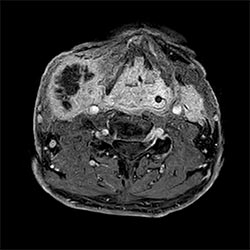

HeadNeck